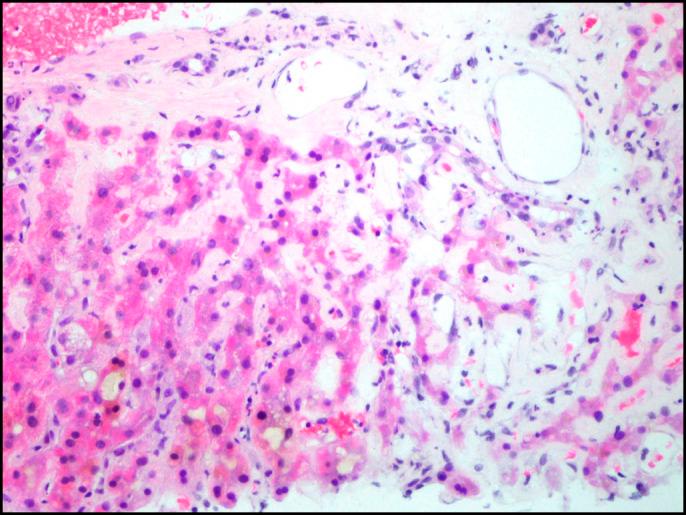

Although hepatic involvement in light chain-associated amyloidosis is common, clinical manifestations of hepatic amyloidosis are rare. In most cases, hepatomegaly serves as a clue to diagnosis. We report a unique case of a 48-year-old man from China with jaundice and noncirrhotic portal hypertension, with rapidly progressive liver failure, in the absence of hepatomegaly, secondary to systemic light chain-associated amyloidosis associated with multiple myeloma.

尽管轻链相关性淀粉样变性累及肝脏很常见,但肝淀粉样变性的临床表现却很少见。在大多数情况下,肝肿大是诊断的线索。我们报告了一例独特的病例,一名来自中国的48岁男性,患有黄疸和非肝硬化性门静脉高压症,继发于与多发性骨髓瘤相关的系统性轻链相关性淀粉样变性,在没有肝肿大的情况下出现快速进展的肝功能衰竭。